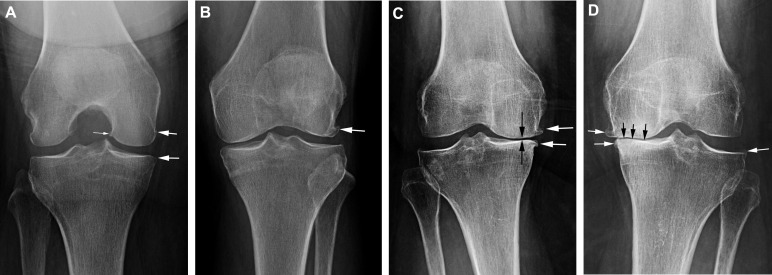

شدت آرتروز زانو

ساییدگی زانو اغلب در افراد مسن مشاهده می شود. اما ممکن است به خاطر آسیب دیدگی یا ژنتیک در بین افراد جوان هم اتفاق می افتد. این مشکل جز بیماری های پیشرونده است که دارای ۵ مرحله می باشد. مرحله صفر آن یعنی مفصل کاملاً سالم است و میتواند فعالیتهای عادی خود را به خوبی انجام دهد. ولی مرحله چهارم نشان دهنده شدیدترین نوع آرتروز زانو است. افرادی که دچار آرتروز شدید زانو هستند، غضروفشان در چند ناحیه کاملاً از بین رفته و استهلاک استخوان ها بسیار شدید است و با علائم گفته شده در زیر مواجه هستند:

تشخیص آرتروز زانو چگونه انجام می شود؟

متخصص آرتروز زانو ابتدا با بررسی سابقه پزشکی و معاینه فیزیکی و انجام بررسی های تشخیصی لازم به تشخیص آرتروز می پردازد. البته اولین کسی که شما در مورد آرتروز و درد مفصل با او صحبت می کنید پزشک عمومی است. او با بررسی سابقه پزشکی و علائمی که شما برای او مطرح می کنید جهت کاهش درد دارو تجویز و برای بررسی های لازم و درمان دقیق تر، شما را نزد پزشک متخصص معرفی می کند.

آزمایش هایی که جهت تشخیص درست آرتروز تجویز می شود، شامل موارد زیر می باشد:

- اشعه ایکس یا گرافی